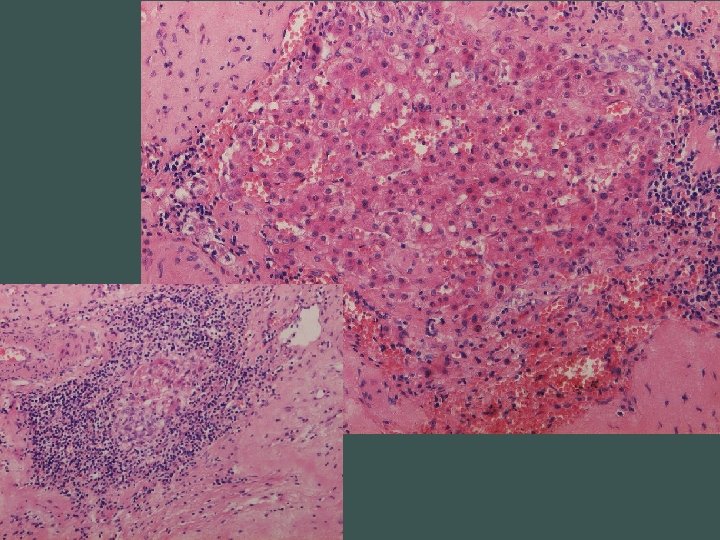

Segmentálna atrofia pečene • zriedkavý pseudotumor • častejšie u žien, unifokálny • najčastejší príznak bolesť horného pravého kvadrantu • prevažne subkapsulárne • 1, 8 - 10 cm • abnormálne hrubostenné cievy (len intralezionálne), často trombotizované, rekanalizované • biliárne cysty

Stage 1 - 4 • 1 – kolaps parenchýmu so zachovaním portálnych polí, občasnými ostrovčekmi zachovaného parenchýmu a s duktulárnou reakciou • 2 – minimálna až žiadna duktulárna reakcia, zvýšená miera elastózy • 3 – takmer výlučne elastóza, občasné malé ostrovčeky hepatocytov • 4 – end stage, ložisko fibrózy

Dif. dg. • amyloidóza • epiteloidný hemangioendotelióm • cancer- asociovaná elastóza (cholangio CA, MTS adeno CA)